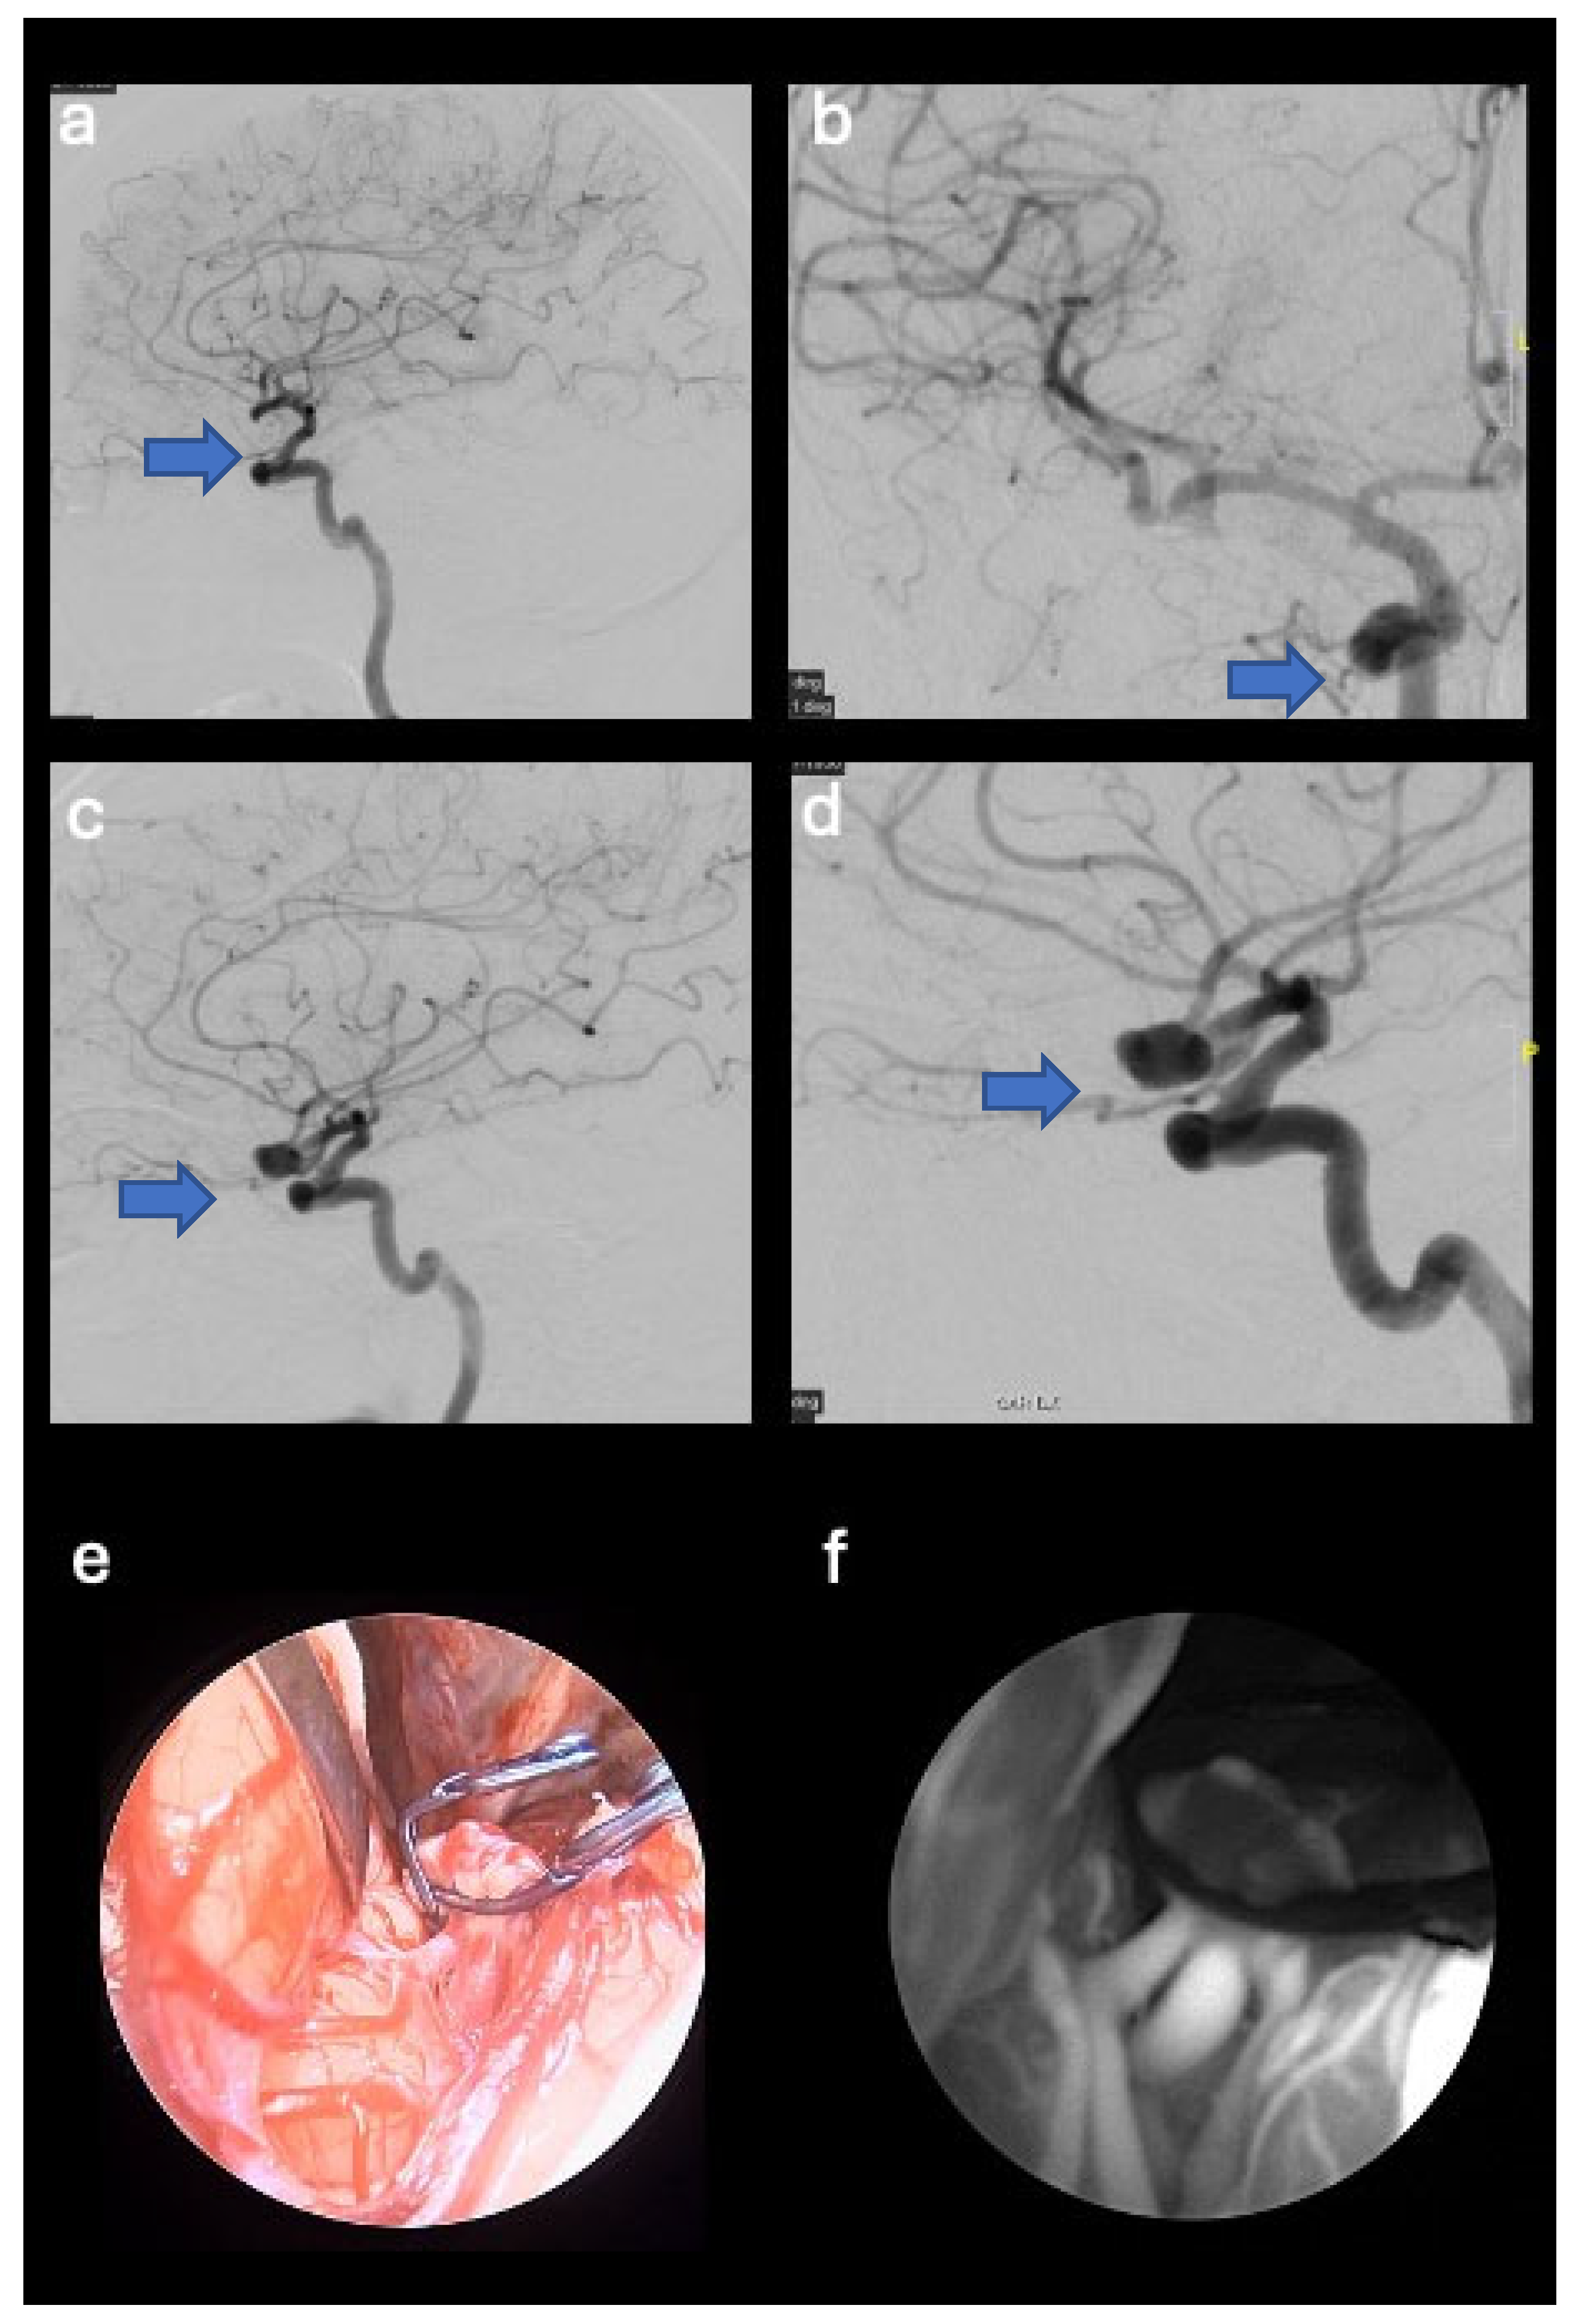

- A 73-year-old female patient with temporal AVM originating from the left middle cerebral artery and discharge into the ipsilateral transverse sinus, with a 3 cm nidus. The AVM manifested itself with an episode of fluent aphasia. The patient underwent preoperative embolization and microsurgical removal of the nidus (see Figure 1).

3.2.1. Case Number 2

| 2 | 73 | F | Episode of fluent aphasia | Left temporal AVM originating from the left middle cerebral artery and venous drainage into the ipsilateral transverse sinus (3 cm nidus) | Preoperative embolization and the microsurgical removal of the nidus | Complete removal of the nidus and transient fluent aphasia lasting three months; no bleeding events. |